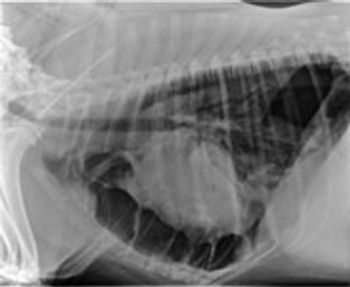

Megaesophagus is a condition in which the esophagus has reduced peristalsis, and has poor tone at rest. The esophagus can have a mild, focal motility problem, or the entire organ may be dilated and functioning poorly.